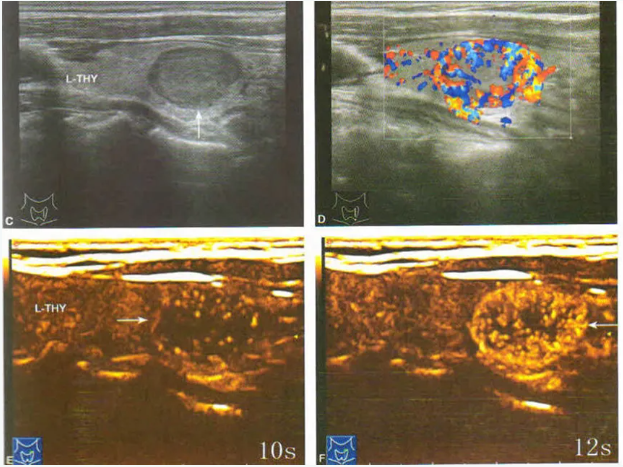

超声造影的造影剂能够增强人体血流信号,便于超声观察组织微血管灌注信息,提高病变的检出率以及良恶性的鉴别,可清晰显示微细血管,特别是肿瘤血管的新型显像技术,可用于肝脏、胆囊、甲状腺、乳腺、肾脏、膀胱、前列腺、子宫附件等器官内占位性病灶等做定性诊断。